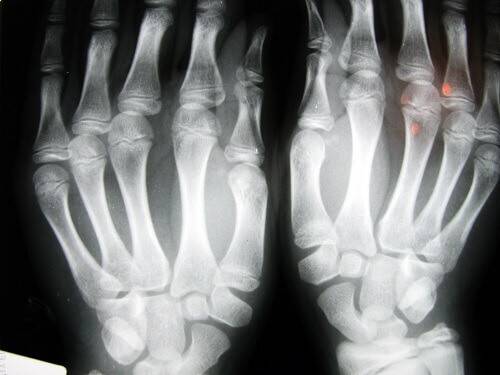

Знаменитые врачи Castellanos J. и Axelrod D. при написании своей книги “Летопись Ревматического заболевания” (1990г) провели исследования по влиянию хруста пальцев, на основании рентгеновских снимков, доказывают, что эта привычка приводит к опуханию суставов и деформации пальцев.